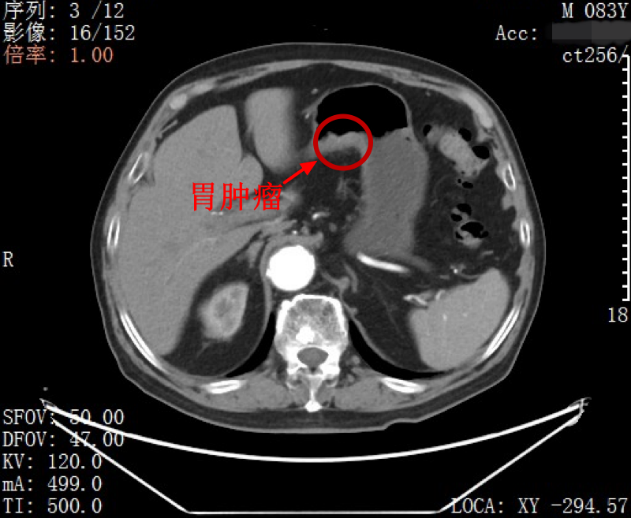

多方了解之后,家人带着叶先生来到北大深圳医院胃肠外科就医,通过进一步完善检查,科室主任吕国庆医生与团队详细分析了叶先生的病情:一是患者的两处肿瘤并没有关联,均为独立的原发肿瘤,没有发生肿瘤转移。病理结果提示:患者胃部的不规则溃疡为中期管状腺癌;乙状结肠则有一个 4.9 厘米×4.5 厘米大小的中期腺癌。叶先生两处肿瘤均未发生转移,还有手术切除的机会。

吕国庆主任带领包括敖胜医生、李冠医生在内的手术团队,仅在叶先生的肚脐部位切开了 1 个约 4 厘米的切口和 4 个几毫米的小孔,采用 3D 腹腔镜,先是切除了胃部的肿瘤,并将切除的组织从脐部切口取出;再用 3D 腹腔镜深入乙状结肠,切除肿瘤,从脐部切口取出切除的组织,最后吻合肠道,缝合脐部切口。手术过程顺利,4 小时完成,术中几乎无出血。